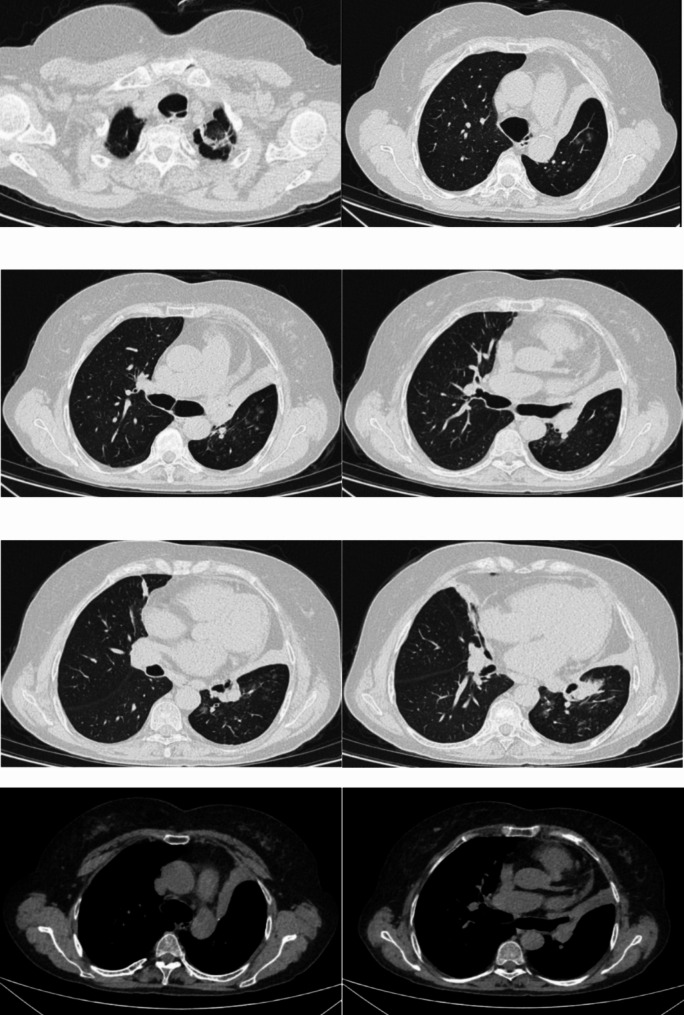

Background: Tracheobronchomegaly, also known as Mounier-Kuhn syndrome (MKS), is a rare congenital condition characterized by significant dilation of the trachea and main bronchi along with an abnormal wall structure. Diagnosis can be confirmed through computed tomography, pulmonary function tests, and diagnostic bronchoscopy. Currently, there is no curative treatment for MKS; thus, symptomatic and supportive care remain the primary therapeutic approaches. Early diagnosis, effective infection control, and individualized management are crucial for improving patient outcomes.

Methods: This case report describes a middle-aged woman who presented with chronic cough, expectoration, and wheezing. She had been misdiagnosed with chronic obstructive pulmonary disease (COPD) at a local hospital for an extended period and was subsequently referred to our institution for fiberoptic bronchoscopy, which confirmed the diagnosis of MKS. By reviewing the literature via PubMed, we conducted a retrospective analysis of 29 previously reported cases of MKS, including the present case, totaling 30 cases (21 males and 9 females), predominantly middle-aged and elderly individuals.